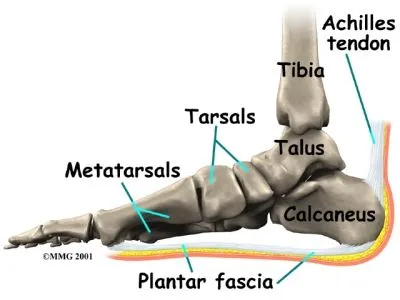

Plantar fasciitis and achilles pain clearance

Plantar fasciitis and achilles pain clearance, Is My Heel Pain Achilles Tendonitis vs Plantar Fasciitis Ease Achilles Heel Pain With These Tips clearance

Plantar fasciitis and achilles pain clearance

Achilles Tendonitis vs. Plantar Fasciitis Which Do I Have Arlington Mansfield Foot Ankle Centers Podiatrists clearance, plantar fasciitis clearance, Heel Pain Causes and Treatment clearance, Achilles Tendon Pain and Plantar Fasciitis Treatment Guide clearance, This Stretch Relieves Plantar Fasciitis Shin Splints Achilles Pain and Heel Pain Focusphysiotherapy clearance, Heel Pain Plantar Fasciitis Delaware Foot and Ankle Group Podiatrist in Newark DE clearance, Plantar Fasciitis and Achilles Tendonopathy InterX Pain Clinic Stratford Upon Avon clearance, Heel Pain Podiatrist Temple Hill Clinton MD Burton J. Katzen DPM clearance, Back of Achilles Tendon Heel Pain Shoes Orthotics Home Treatment clearance, Seattle Bellevue Heel Pain Center Issaquah Foot Ankle Specialists clearance, Interwoven Threads The Plantar Fascia Achilles Tendon Connection clearance, Plantar fasciitis VS Achilles tendinitis Managing Heel Pain Greg Robinson Ibraheem Podiatry clearance, Can Plantar Fasciitis Cause Calf Pain clearance, Plantar fasciitis achilles tendon deals pain clearance, On the morphological relations of the Achilles tendon and plantar fascia via the calcaneus a cadaveric study Scientific Reports clearance, This One Stretch Helps Relieve Plantar Fasciitis Shin Splints Achilles Pain and Heel Pain clearance, Plantar Fasciitis Symptoms and Treatment Doctor clearance, Effective Treatment for Heel Pain Foot Foundation clearance, Plantar Fasciitis Chiropractors in Newmarket ON clearance, Plantar Fasciitis FAQ s clearance, Plantar Fasciitis Symptoms Causes Treatment Options clearance, Is My Heel Pain Achilles Tendonitis vs Plantar Fasciitis Ease Achilles Heel Pain With These Tips clearance, Plantar fasciitis Information Mount Sinai New York clearance, Achilles Tendonitis Plantar Fasciitis clearance, Common Problems that Can Lead to Plantar Fasciitis and Achilles Tendonitis clearance, Heel Pain clearance, Is Plantar Fasciitis Your Achilles Heel Prosper clearance, Plantar Fasciitis Dr7 Physiotherapy Podiatry Hydrotherapy Massage clearance, Foot or Heel Pain It Might Be Plantar Fasciitis Healthy You clearance, Achilles Tendonitis and Plantar Fasciitis Premier Podiatry Velimir Petkov DPM Podiatrists clearance, Achilles Tendonitis Vs Plantar Fasciitis Which Do I Have clearance, Difference between Plantar Fasciitis and Achilles Tendonitis Achieve clearance, Achilles Tendonitis vs. Plantar Fasciitis clearance, Achilles tendonitis vs. plantar fasciitis How to tell the difference clearance, Achilles tendonitis vs. plantar fasciitis How to tell the difference clearance, Product Info: Plantar fasciitis and achilles pain clearance.

Plantar fasciitis and achilles pain clearance

Plantar Fasciitis Symptoms and Treatment Doctor- plantar fasciitis and achilles pain